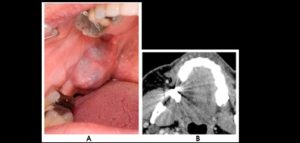

132 – Tratamiento de la reabsorción radicular interna idiopática perforante: controles radiográficos

La reabsorción radicular interna (RRI) es una afección inflamatoria que resulta en la destrucción progresiva de la dentina intra-radicular a lo largo de los tercios